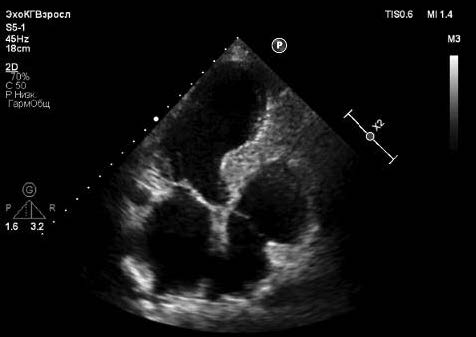

Сигмовидная МЖП – феномен, встречающийся преимущественно в старшей возрастной группе и не имеющий на сегодняшний день однозначного объяснения (рис. 1). Критериями сигмовидной МЖП при эхокардиографическом (ЭхоКГ) исследовании являются: изолированное утолщение проксимальной трети МЖП≥13 у мужчин и ≥12 мм у женщин с дюноподобным провисанием в ВОЛЖ и более чем 50% превышением толщины МЖП в соседнем срединном сегменте [36]. Согласно данным исследований I. Ranasinghe и M. Canepa и соавт. распространенность сигмовидной МЖП среди тех, кому проводится ЭхоКГ по различным показаниям, составляет 6–7% с отчетливой ассоциацией с возрастом и без связи с полом или сопутствующей патологией в виде артериальной гипертензии (АГ), сахарного диабета или ожирения. Средний возраст пациентов с сигмовидной МЖП – 76 лет, а распространенность в возрастной группе старше 78 лет – 17%. У 3% таких больных выявляется обструкция ВОЛЖ. Ни у одного из обследованных 240 больных с сигмовидной МЖП не имелось семейного анамнеза ГКМП, а типичные для ГКМП изменения на электрокардиограмме (ЭКГ) встречаются нечасто (рис. 2) [36, 37]. У больных с изолированной гипертрофией базального отдела МЖП по сравнению с другой морфологией ГКМП реже регистрируется накопление контраста в отсроченную фазу магнитно-резонансной томографии сердца [38].

Рис. 1. Сигмовидная МЖП у больной 94 лет.